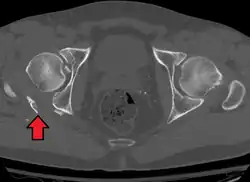

X-ray visualization is best done in Antero posterior view and Iliac and obturator oblique views. In CT scan the characteristic feature is that the fracture line runs from front to back. CT scan also helps in identifying impaction of bone pieces and if there are pieces in the joint

In all cases, CT scan can assist in identifying impacted bone pieces, which may be found within the joint, and MRI may be done to identify the extent of potential injury to the sciatic nerve.